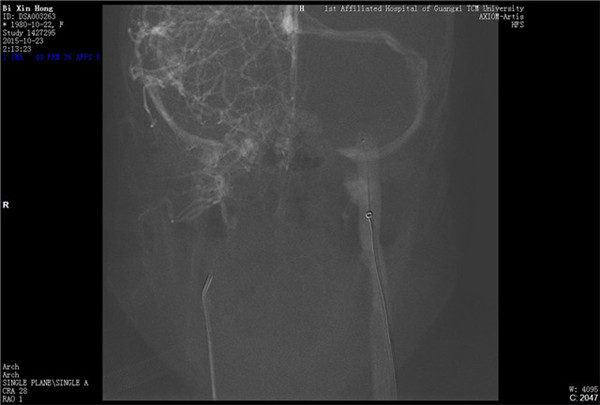

经与患者及家属充分沟通并获得同意后,外六科脑血管病介入治疗团队立即为患者行全脑血管造影,造影结果证实上矢状窦血栓形成,整个上矢状窦完全闭塞,若不采取措施病情很快就会恶化。再次征得家属同意后果断采取微导管介入手术治疗,手术在起病后当晚开始,由于患者血栓位置深在,需要经动、静脉双重途径置管,技术难度较大。术者选取Solitaire支架( 美国 公司)置入微导管远端,释放支架并在原位作短暂停留使支架与血栓充分接触并黏附,一起回撤支架与微导管取出血栓,手术一直持续到第二天凌晨。术后留置导管一条,用于每天以药物继续溶栓。术后患者即清醒,头痛明显缓解,无神经功能缺失。手术第二周时患者已经能够生活自理。2015年12月12日患者痊愈出院。

左颈静脉入路